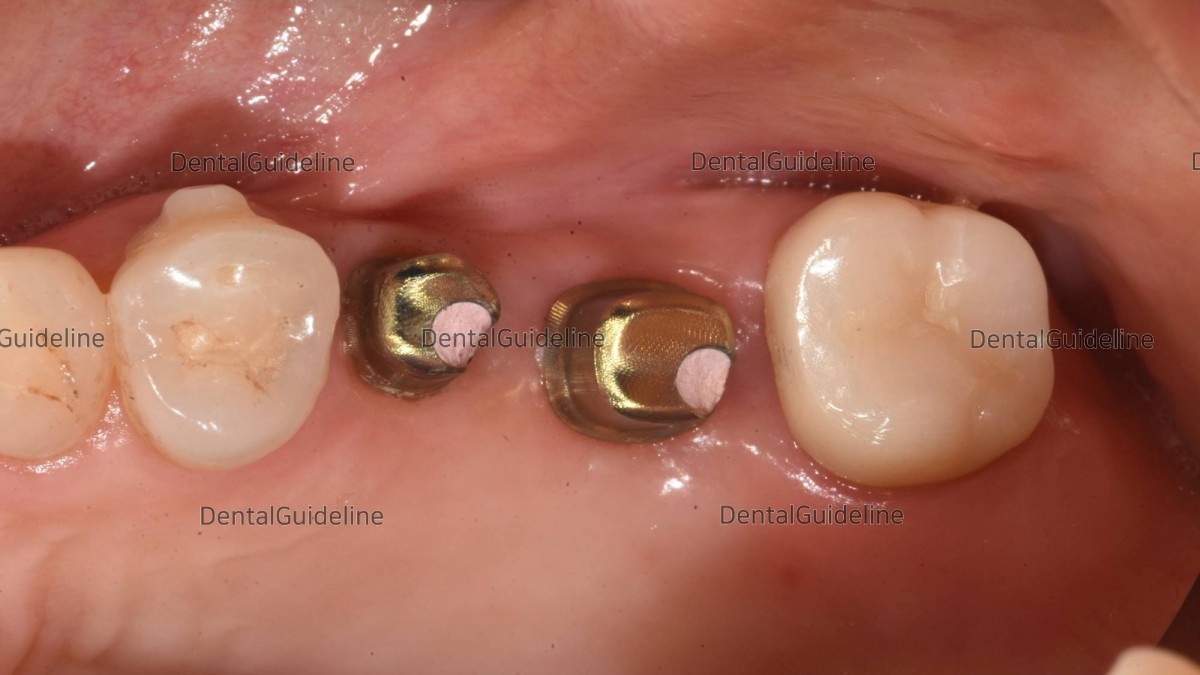

4. Intra-oral photo was taken on the day of implant placement.

16. Scan-abutments were connected for digital impressions.